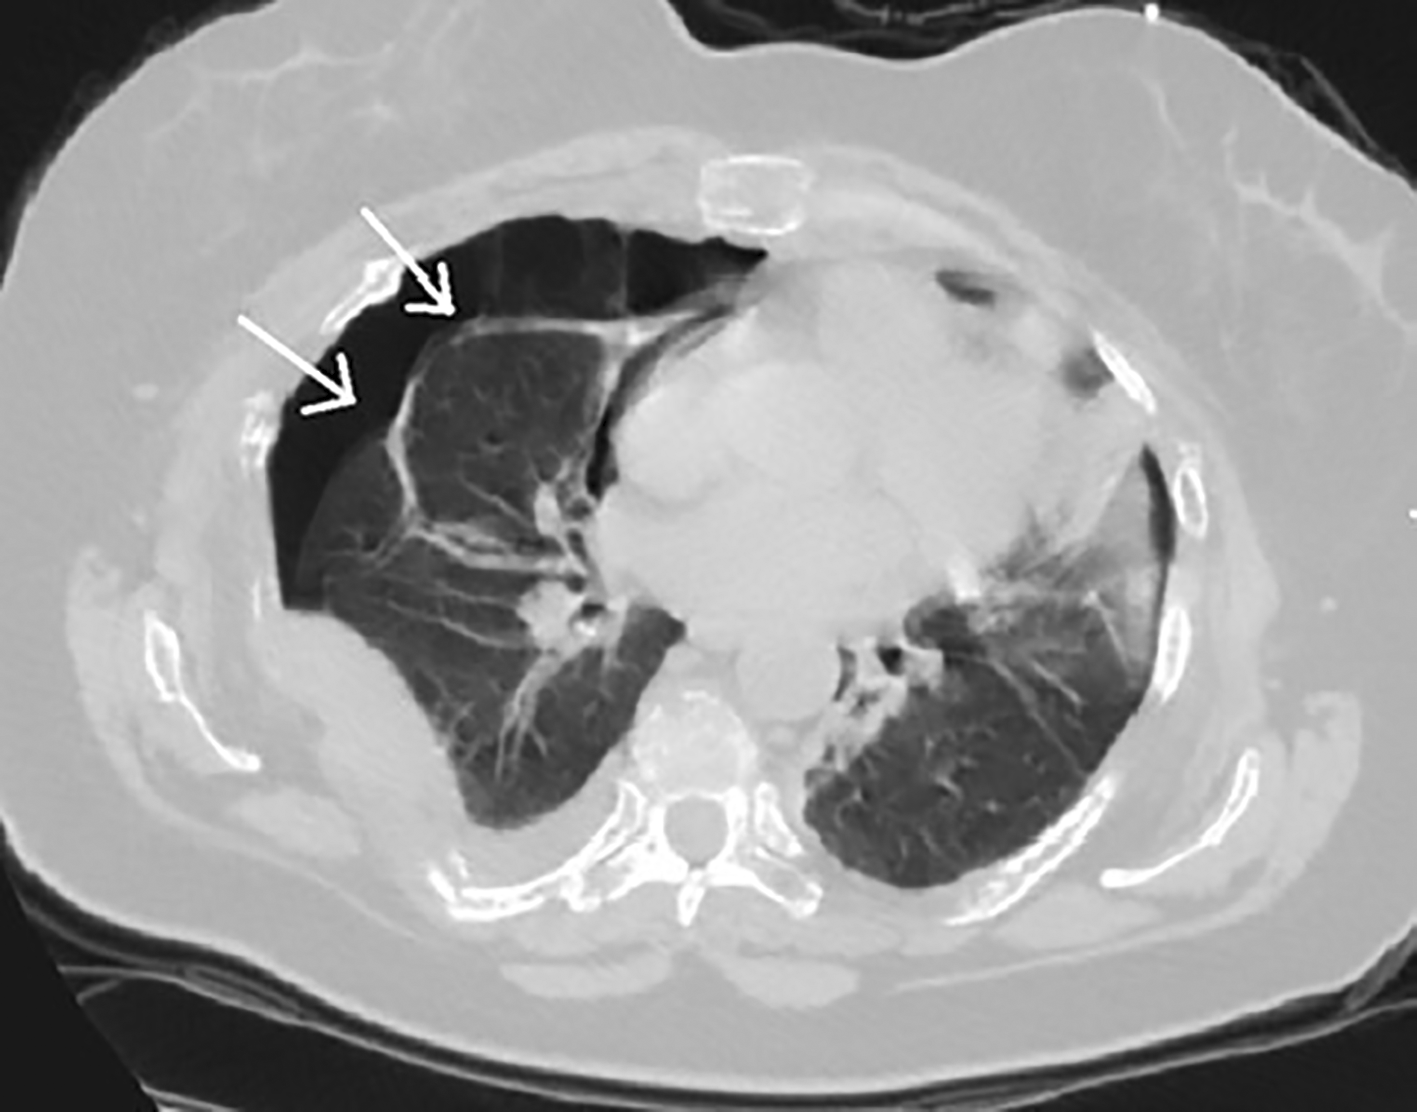

Chest radiography and thoracic computed tomography revealed multiple ribs and sternum fractures leading to a partial pneumothorax on the right side (Figures 1, 2). She also had objective spine fractures localized in the T8, T9 and T10 vertebrae.

Multiple myeloma is an hemopathy with excessive bone resorption, leading to single or multiple osteolytic lesions.4 About 85% of patients with Multiple myeloma show some degree of osteopenia at the moment of diagnosis. The severity of bone destruction is frequently correlated with the tumor burden and the Multiple myeloma prognosis.5 In our case, the rib fractures were the cause of a pneumothorax leading to an acute respiratory failure. These rib fractures were characterized by a periosteal callus which was predominant in the ventral side of the chest. The same appearance of rib fracture has been shown in an autopsy study in fatal child abuse cases.6 It has been suggested that the mechanism of this pneumothorax is due to the bending of the rib against the transverse process, acting as a fulcrum and leading to spontaneous rib fracture. Also, such fractures suggest that the mechanism of injury is not a direct trauma.7 Although, as reported in thoracic injury from blunt force trauma, rib fracture can puncture the lungs and the pleural sac, leading to a pneumothorax, a life-threatening complication.7